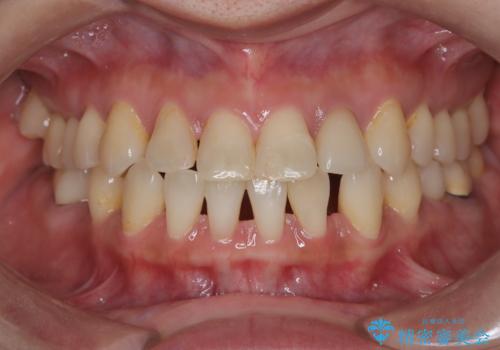

突き出た前歯を下げて理想的な横顔に。上下左右4番抜歯による審美ワイヤー矯正